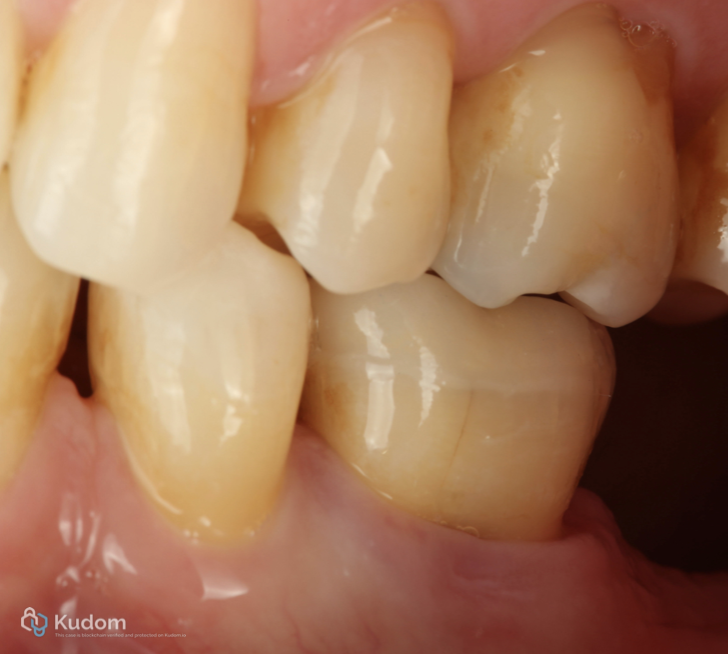

Fig. 2

Initial clinical situation

Fig. 3

. Tooth 3.6 with irreversible pulpitis.

. Occlusal structural loss.